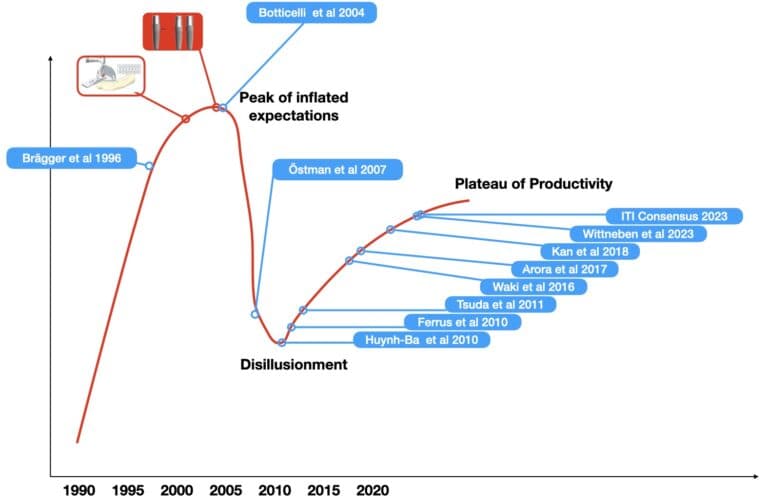

Implants placed in fresh extraction sockets were first documented more than 25 years ago, so one might wonder why “immediacy” took so long time to mature into the mainstream implantology. The progress of a scientific protocol however, is rarely a straight line to implementation. Perceived breakthroughs are often followed by backlash and enthusiasm can be at times interchangeable with periods of caution. In the end, technology is also a major catalyst to help a vision make it safe to the mainstream practice.

If you think that immediate implants are a cool new development, better think twice: it was a hot research topic already in the 90’s and scarily enough, this is already 30 years ago..! Back in 1996, NP Lang the founding editor of Clin Oral Imp Res after an exhaustively detailed study was concluding that “immediate implants are feasible treatment modality with high predictability”, while also documenting less bleeding on probing around immediate than conventionally placed implants. Back then he was placing the “ITI implants” in fresh extraction sockets with or without guided bone regeneration and transmucosal healing. Well ahead of its time you might think. Interestingly, by the time I joined his department in 2005 he was rather critical of immediate implants, and so would also remember him most of our Hong Kong colleagues and students. To think of what could have possibly happened, let’s get back to 1996 and follow the steps of an exciting journey.

Although publications about immediate implants were appearing all through the 90’s, long term evaluations start to show towards the end of the decade. In 1997, Schwarz-Arad and Chausu published 4-7 years follow up of 95 immediate implants placed with submerged healing and showed a very good survival rate of 94.7 %. Just a year later, in 1998 the same authors growing obviously encouraged by the documented success, they take the method one step further and publish 9 cases where the implants were placed flapless in the extraction sockets, augmented with autogenous chips and left to heal transmucosally with only some retaining sutures. And guess what, it all worked well.

By the time I start my own journey in Implant Dentistry around the turn of the millennium, the euphoria on immediates continues and Brånemark publishes his first “guided surgery” system in the inaugural issue of Clin Implant Dent and Rel Research. His system is called “Brånemark Novum” and I think it is the predecessor of all static computer assisted implant surgery we use today. Thanks to a prefabricated surgical guide and drill sleeves, implants are placed in position for immediate loading in the mandible. Thus, another immediacy other than the fresh extraction socket is widely introduced: the immediate loading. Two volumes later in the same journal in 2001 our own Dr. James Chow published some exciting results on immediately placed anterior implants restored with immediate provisional crowns. In a 15 month report on 24 implants, survival was 100%, bone loss minimal and aesthetic results high. Does all this sound familiar? Maybe a little feeling of back to the future? The fact is that immediacy was really hot research topic around the turn of the millenia, including some leading ITI researchers. But then how come it took another 24 years before ITI finally reached a favourable consensus on A1 type immediacy?

We are around 2004. The expectations from immediacy peak in the world of implant dentistry, almost as much as the expectations for Olympic medals in Athens. A critical mass of high-profile researchers is convinced that immediate is the way to go to prevent tissue loss and envision immediacy into the mainstream as the new norm. There is a lot of scepticism, but opposition is scarce and criticism rare. The stage is set, for the next move: a breakthrough or a major disaster…

The disillusionment

The first hints of the brewing trouble came through the research work of Daniele Botticcelli during 2004-2006, when he was completing his PhD with Jan Lindhe in Gotehnburg. In a series of well-designed animal experiments, they challenged the perception that immediate implants preserve bone and showed beyond doubt how the early bone resorbtion which takes place through the concept of the bundle bone is inevitable and irrelevant to the implant presence or not. The bundle bone is a biological concept which nobody tilll then had seemed to pay much attention to and which in essence was based on the obvious: the periodontal structures develop together with the tooth and they follow it in oblivion after extraction. In some further experiments the same authors introduced some very important parametres of immediate placement such as the “jumping distance”, the position of the implant and the need of augmentation to counter resorption. (Small parenthesis here, tribute to the legend of Jan Lindhe from Gothenburg who I believe is the man still around with the greatest qualitative impact in periodontology and the biology of Implant Dentistry. You might not hear of him that often and you will hardly see his name in consensus papers and guidelines that by now circulate almost annually from different directions. But from the start till the end, he in my mind is the one who more than anyone changed our thinking at critical times with few, targeted, well designed interventions. Parenthesis closed – back to 2004).

After the studies of Botticelli, the debate started to get more heated and opposing camps formed. In the years between 2004-2007 immediacy is being both enthusiastically promoted and increasingly challenged. Then one clinical study comes to finally tip the scale towards the disillusionment. Östman et al 2007 from the group of implantology pioneers Sennerby and Albrektson, documented a chilling realisation: It doesn’t seem to work as we expected… In a clinical study with 48 patients and 115 one-piece implants the clinical outcomes one year after immediate placement and provisionalisation were alarming: Recession and exposure of rough surface was frequently encountered, as well as bone defects filled with granulation tissue, suppuration, dark shades under the mucosa and failures. All in all, the success of the one-piece immediate implants was alarmingly lower than the two piece counterparts.

The turning point was reached and the actions that unfolded next in the drama turned the tide completely. In the years that followed, a class action filed by more than 2,900 dentists in US lead to a wide debate that saw in the end the Direct and Perfect implants being discontinued and a settlement for a large sum being reached around 2013. Immediacy, which was just about to hit the wider adoption of the mainstream, was now to be put back to hibernation and return to the safety of confined research centres and expert clinicians for further improvement. We were not back to square 1, but indeed, we had taken quite a few steps back. It is around that time that NP Lang establishes the centre of excellence in implant dentistry in Hong Kong, where immediates will be put on ice for a few years more.

Looking back, we can’t help but recognise a well-known pattern, the Hype Cycle of New technologies, as proposed by the Gardner group. Innovation, comes with a cascading effect: as the first outcomes reinforce our perceptions, expectations rise exponentially from the new protocols, expectations however which are not always founded in solid data. The technology delivers, but the novelty effect and some bias makes our expectations to inflate fast and disproportionally to the actual potential, reaching a euphoric peak just at the point of wider adoption. Then as more and more people jump on the wagon, limitations are becoming more apparent, failures inevitably raise, flawed assumptions are laid bare, mistakes are done and a rapid disillusionment curve crushes down in process painful for many. And there, at the rock-bottom is where reflection starts. Data get scrutinised, questions are being formed, myth is slowly being separated from reality. And the slow progress comes towards the plateau of productivity, where the new technology can now deliver under a better designed and understood realistic framework.

Having hit the rock-bottom in the early 10’s, a slow and well controlled process of research and development was initiated. Carefully designed clinical studies by many groups offered critical insights of the biological processes within immediacy, the tissue reactions that take place and under which parametres. How the bone and the soft tissue truly respond to immediate protocols was deciphered little by little through clinical research of that time around the world. To name only few of the teams that contributed to our new understandind I could mention Pjeturrson and Lang in Bern, Joseph Kan and his team in USA, in Gothenburg Lindhe and his associates, Dennis Tarnow and his team in USA and later also our team in Australia with Saso Ivanovski and many more great teams. In the end, the addition of some critical technologies such as 3D implant planning, CAD/CAM components and Computer Assisted Implant Surgery came to supplement our increased biological understanding and develop the modern concept of “immediacy” which is now an entire workflow, extending well before and after the placement of implants in extraction sockets. Immediacy is again about to hit the mainstream, only now from a very different perspective. But let’s make a pause here.